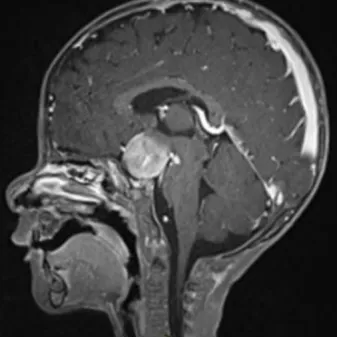

15月大的婴儿,由于生长发育障碍经检查后发现为视神经胶质瘤。尽管病变已经浸润到了视交叉-下丘脑和间脑结构,但所幸并未累及视神经和脑下垂体,未发生脑积水。

很快,医生通过右侧翼点途径对肿瘤进行了直达方式手术,然而,由于患者过于年幼,第一次术后的MRI显示肿瘤仅被有限切除,其尺寸基本没有变化(3.0 x 2.4 x 2.2厘米)。

最终患儿被诊断为毛细胞性星形细胞瘤KIAA1549-BRAF阳性。于2021年8月2日开始化疗,采用了基于长春新碱和卡铂联合治疗的LGG方案。